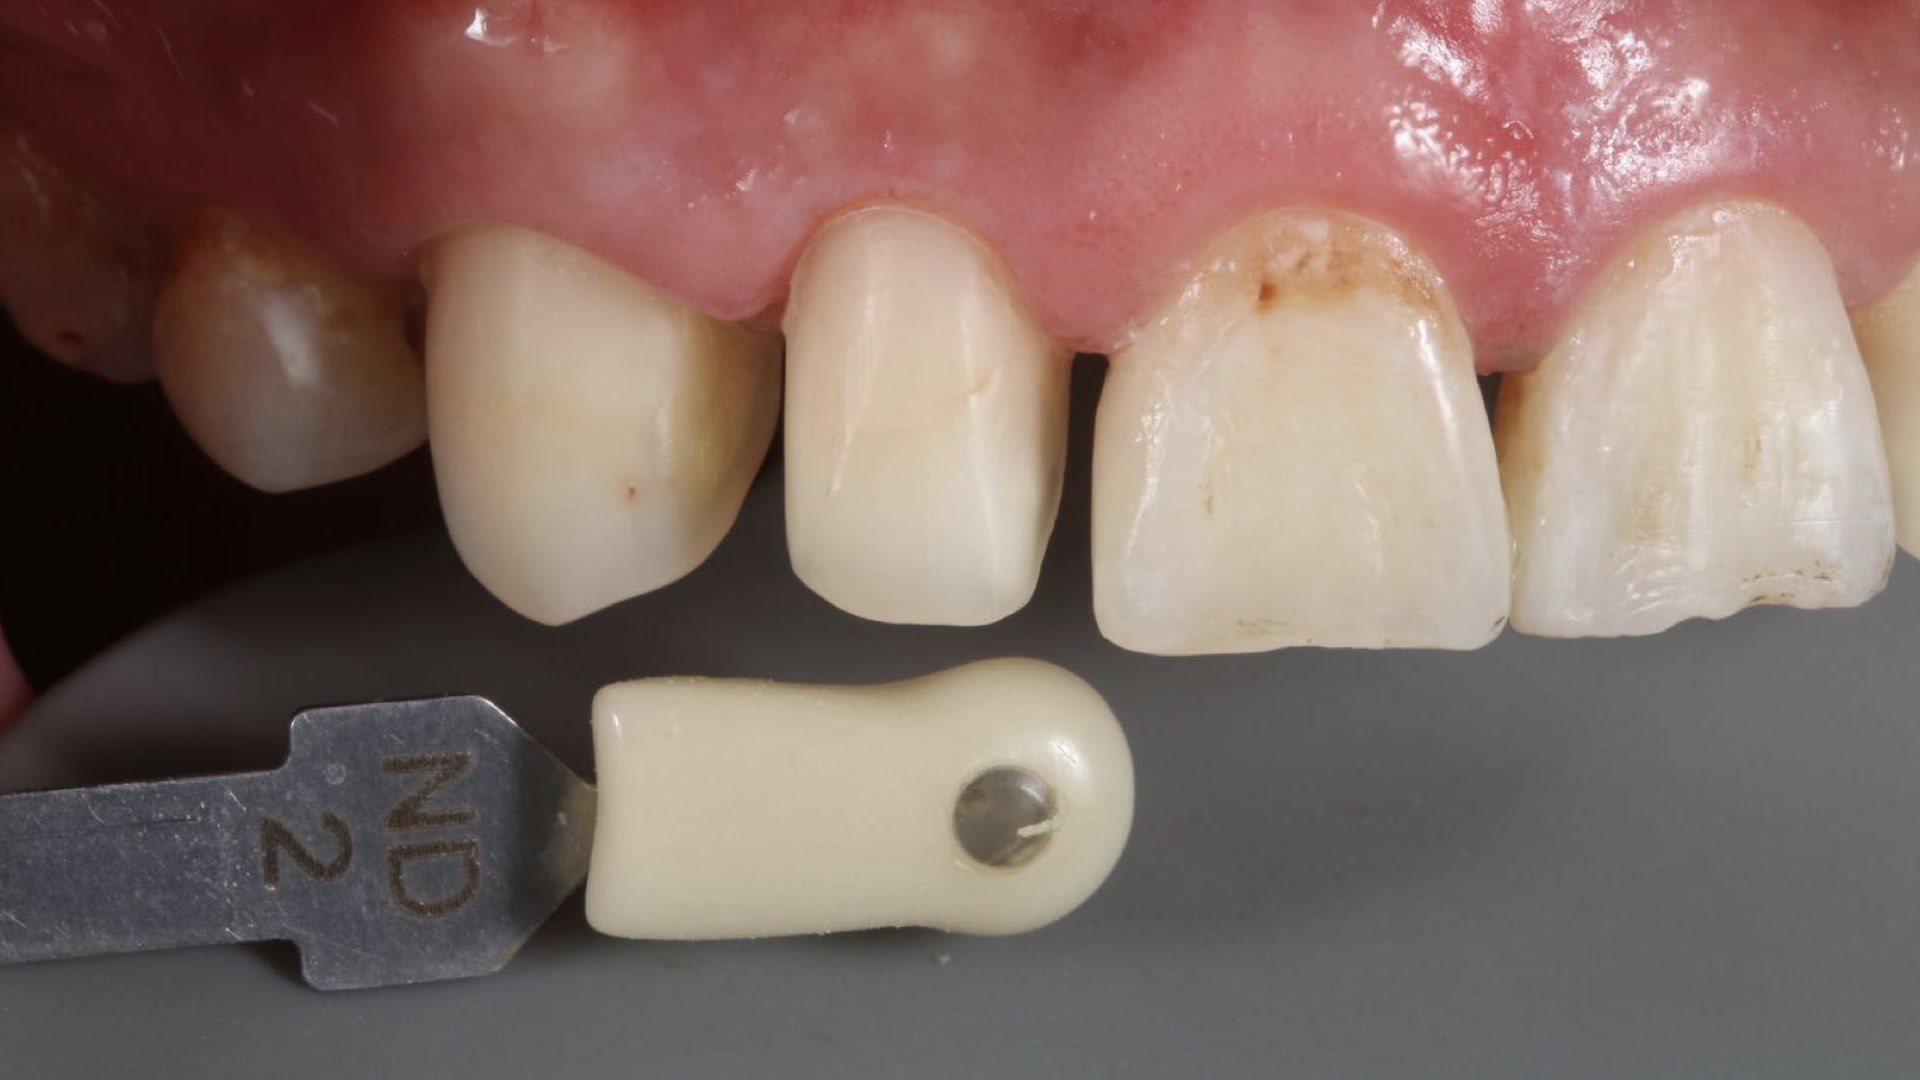

贴面|E.Max .13.12.22.23

温州佳洁口腔 朱照鸿医生 | 技师:贾永青